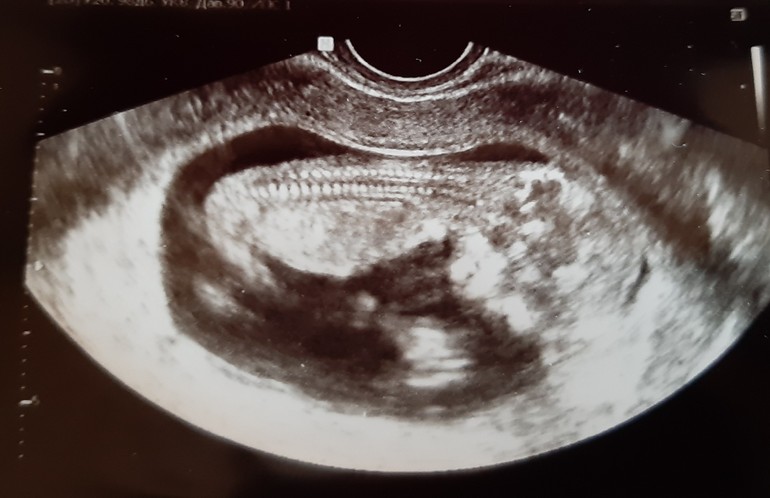

Вопросы про УЗИ, обследования и анализы: что, где, как, когда?Тянуть не буду, вот он, мой малыш!

Результаты сказали нормальные, единственное, что низкое прикрепление плаценты, буду надеяться, что поднимется ко второму скринингу.

Предположили, что мальчик, но пока совсем не точно :) Я не расстроюсь, если подтвердится, но вообще надеюсь на девочку))